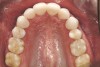

Figure 5a  A 22-year-old female presented, concerned about smile, overbite, and baby tooth. Facial views reveal excellent skeletal components with excessive gingival display and insufficient lip support. Anterior deep bite with extruded and retruded anterior dentition secondary to unstable relationship.

Figure 5a

Figure 5b  A 22-year-old female presented, concerned about smile, overbite, and baby tooth. Facial views reveal excellent skeletal components with excessive gingival display and insufficient lip support (A and B). Anterior deep bite with extruded and retruded anterior dentition secondary to unstable relationship.

Figure 2b

Figure 5c  Note lack of alveolar development from congenitally missing Nos. 24 and 25. Surgical procedures after 5 months of orthodontic alignment included single-tooth osteotomies Nos. 6 to 11 and Nos. 21 to 28 and buccal corticotomies on all other teeth. Anchorage plate was stabilized to piriform rim.

Figure 5c

Figure 5d  Note lack of alveolar development from congenitally missing Nos. 24 and 25. Surgical procedures after 5 months of orthodontic alignment included single-tooth osteotomies Nos. 6 to 11 and Nos. 21 to 28 and buccal corticotomies on all other teeth. Anchorage plate was stabilized to piriform rim.

Figure 5d

Figure 5e  Anchorage plate was stabilized to piriform rim (E through H). Final result 12 months postsurgery (F). There is significant lateral dentoalveolar expansion of arches and alveoloskeletal correction in maxillary and mandibular anterior regions. Alveolar bone volume was increased in lower anterior to create optimal implant sites and establish ideal interincisal function and stability.

Figure 5e

Figure 5f  Anchorage plate was stabilized to piriform rim (E through H). Final result 12 months postsurgery (F). There is significant lateral dentoalveolar expansion of arches and alveoloskeletal correction in maxillary and mandibular anterior regions. Alveolar bone volume was increased in lower anterior to create optimal implant sites and establish ideal interincisal function and stability.

Figure 5f

Figure 5g

Figure 5h  Final facial views show significant esthetic enhancements with broader maxillary arch, correction of “gummy smile,” and fuller lip support (I and J). Restorative dentist: John L. Garlinghouse, DMD.

Figure 5h

Figure 5i  Final facial views show significant esthetic enhancements with broader maxillary arch, correction of “gummy smile,” and fuller lip support (I and J). Restorative dentist: John L. Garlinghouse, DMD.

Figure 5i